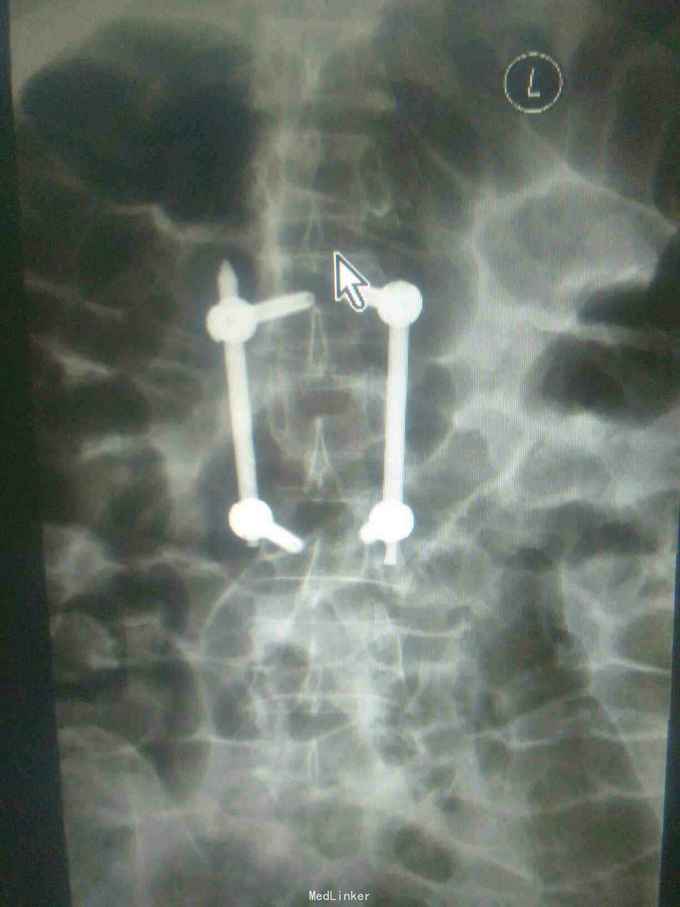

一例腰椎骨折行经皮椎弓根钉内固定术

诊断:腰2椎体压缩性骨折。手术:于插管全麻下行经皮椎弓根钉内固定术。

第一次做,请指教。钉子长了点,棒短了点,但没出。除此之外,还有哪些欠缺。